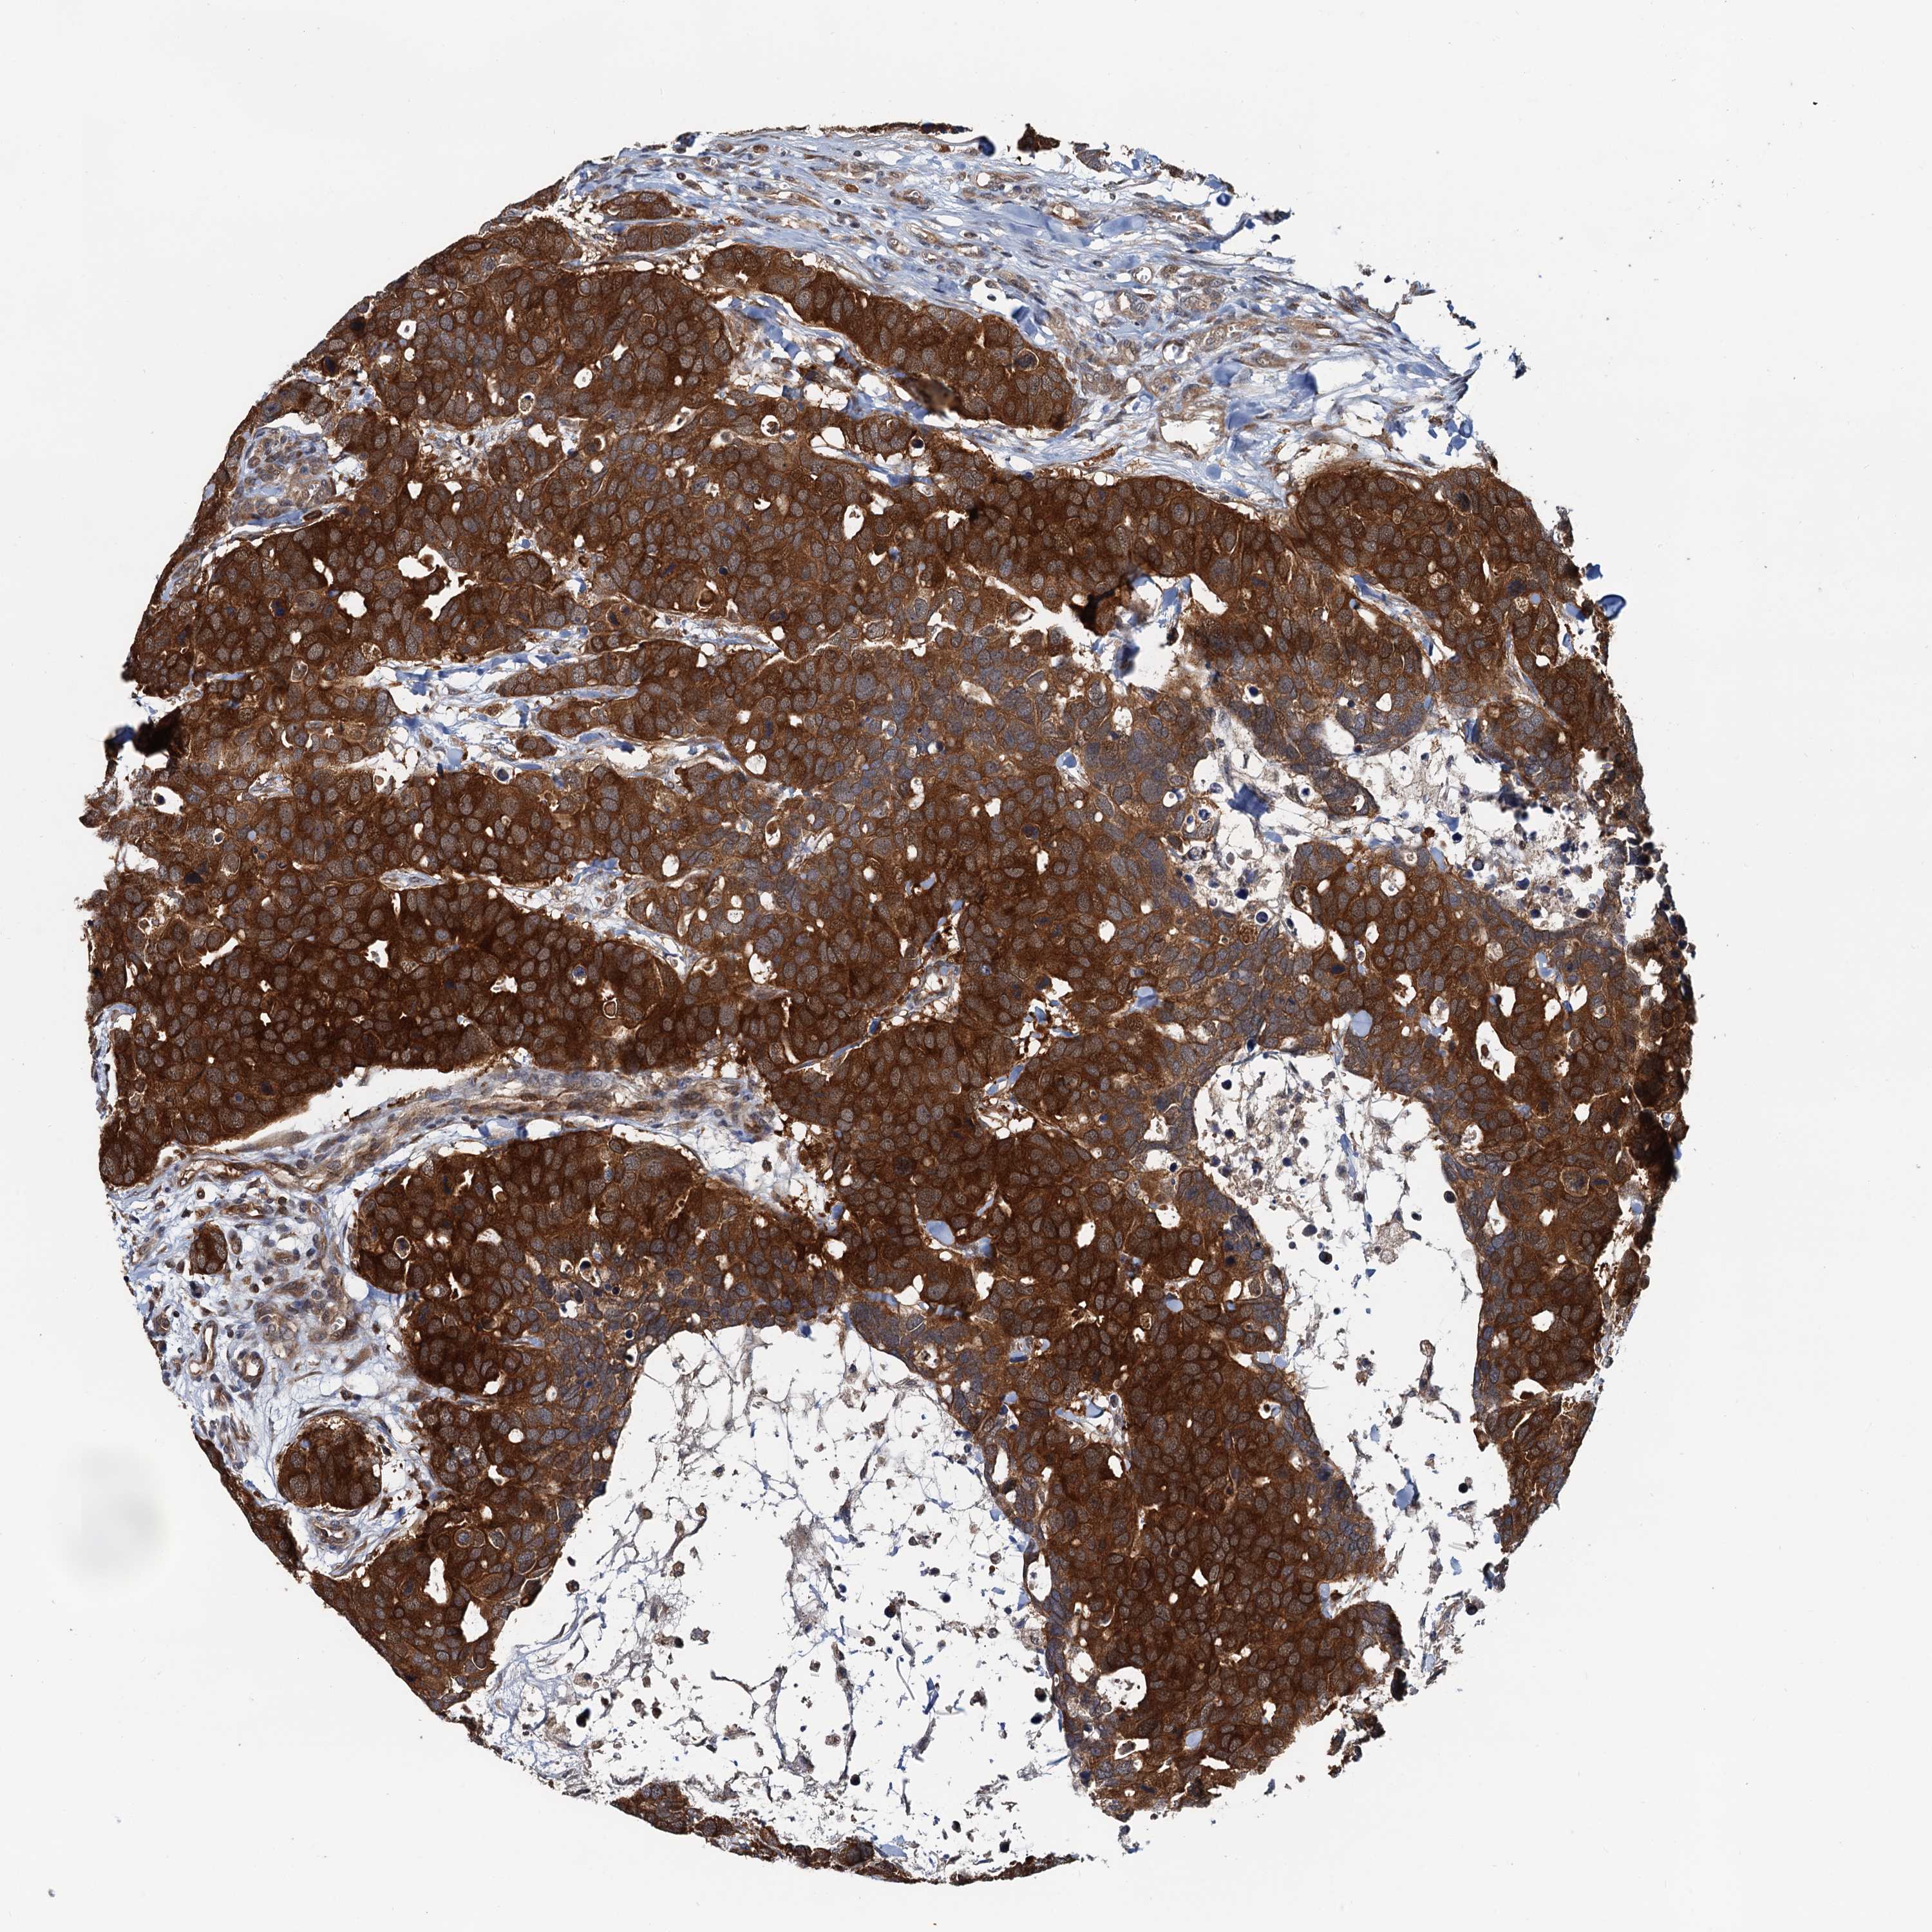

CANCER BREAST CANCER Show tissue menu

BRCA TCGA BRCA VALIDATION PROTEIN EXPRESSION